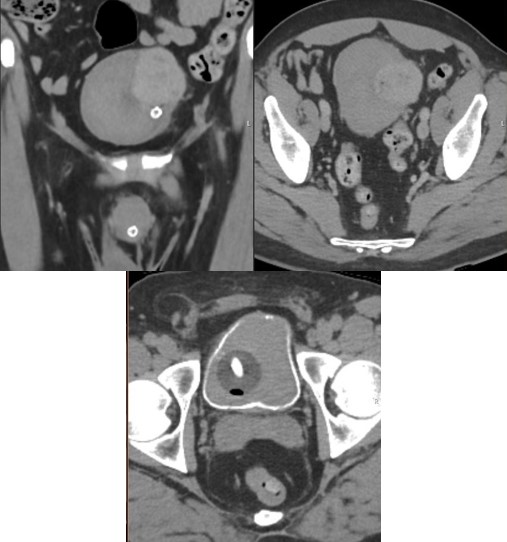

The patient subsequently had cystoscopy, left JJ stent insertion, and robot-assisted enucleation of the bladder mass. Intraoperatively, the lesion appeared well encapsulated with well demarcated margin between the bladder muscle and the mass. Therefore, mass was enucleated to maximise bladder preservation and avoid need for ureteric reimplantation. This entailed combination of sharp and blunt dissection to peel the lesion off the bladder wall (Figure 2).

A drain was placed at the end of the procedure which was removed next day. Patient was discharged on day 2 after the procedure with catheter in-situ. Cystogram performed 3 weeks later showed no leak and had successful the trial without catheter.

Figure 2: Intra-operative laparoscopic view demonstrating a well encapsulated mass (top) being enucleated off the bladder wall’s detrusor fibres through a cystostomy incision; (A) bladder mass, (B) bladder wall, (C) inside of the bladder and (D) peri-vesical fat. Photos have been edited to enhance tissue differentiation from original photos (on the right).

Figure 3: Cystogram showing no leakage with reflux of contrast over left JJ stent to the left kidney.